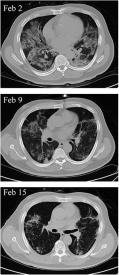

In this section we will focus on an example based on the COVID-19 pneumonia invading and fading away process in a patient’s lung reflected on CT scan images and try to show the possible COVID-19 pneumonia growth dynamics with time before and after the treatment. In order to fulfill the task, two parts of simulations are presented. In the first part, two CT scan images taken on a patient’s lungs in the beginning (January 23th) and severe state (February 2nd) of the disease [ZL20] are selected to be the initial and equilibrium state, respectively; see Fig. 3 (left). In the second part, two scan images at the severe state (February 2nd) and after a few-days’ treatment (February 9th) are selected to be the initial and equilibrium state, respectively; see Fig. 3 (right). Each CT scan image can be represented by a gray scale image matrix thus the same method in Example I can be applied. The CT scan images are all cropped to 461 pixels in width and 370 pixels in height, which means a total of 170570 pixel points in each image. The time step is and the total number of iterations is thus the final iteration time . The resolutions are .

After 6000 iterations, the relative root mean square errors from two parts of simulations both decrease with an exponential rate, as is shown in Fig. 4. Moreover, the image evolution after step 20, 50, 100, , , 1000, 5000, 10000 (see Fig. 5) clearly demonstrate the pneumonia invading process into the patient’s lungs caused by COVID-19 in a few days (upper group of figures in Fig. 5) and the pneumonia fading away from the lungs after a stem cell treatment is applied to the patient (lower group of figures in Fig. 5), indicating a potential success of this treatment [ZL20]. We can further compare the evolution process with the real CT scan images taken on January 30th (see Fig. 3) and find satisfactory agreements, which indicates promising applications in this field.